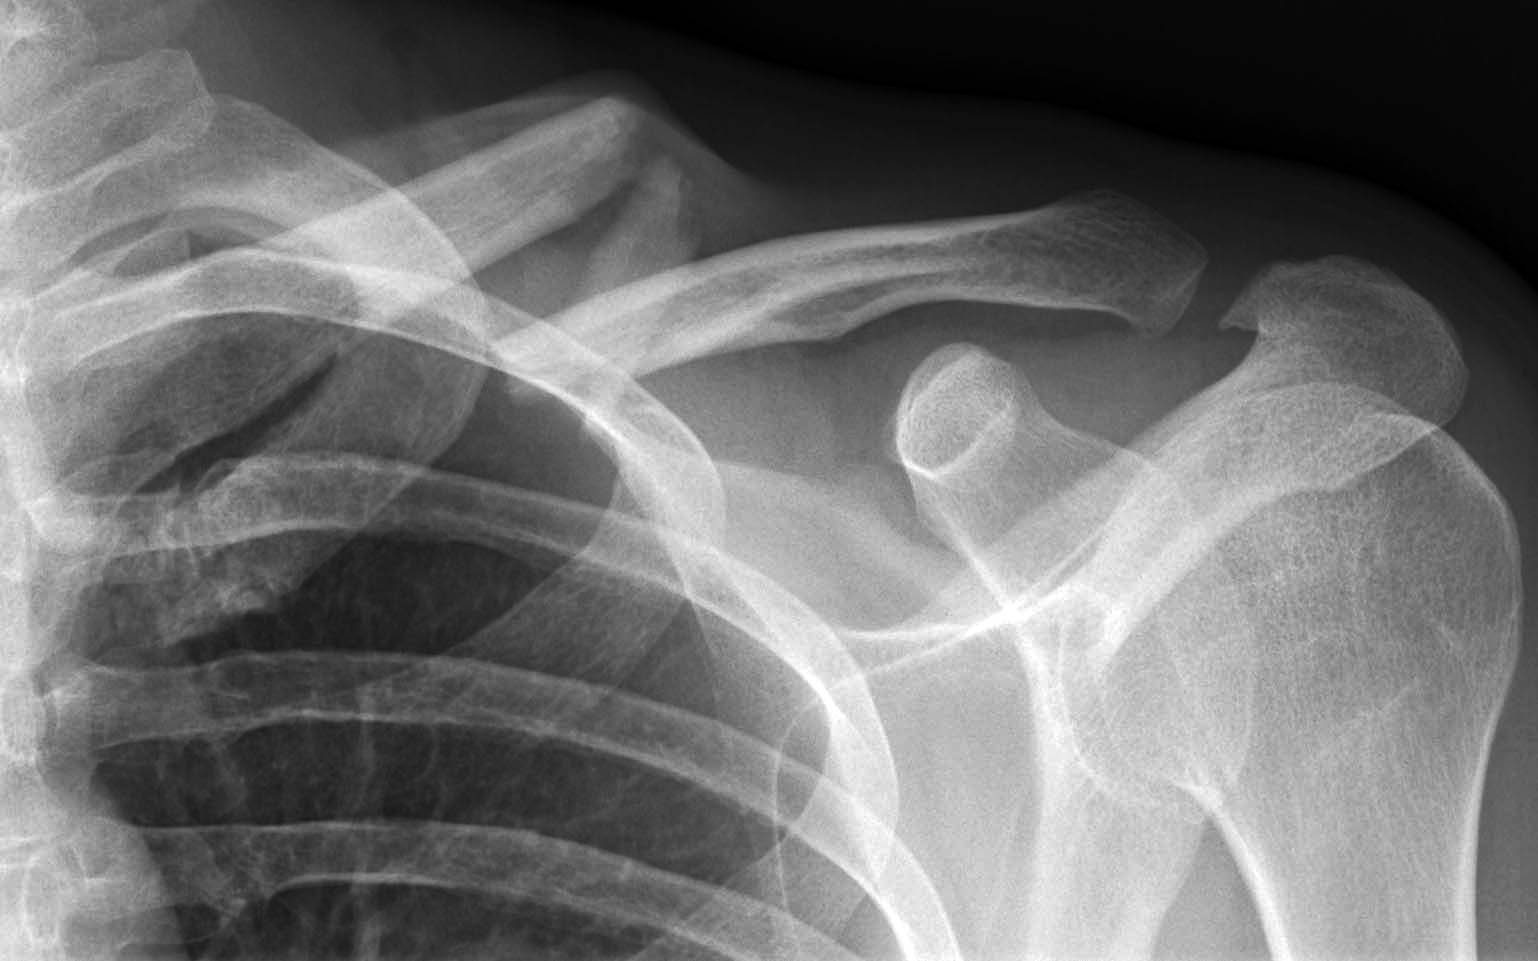

Une réception un peu courte sur un saut, la roue avant qui se cale dans un trou ou une marche plus grosse que prévu et hop, on bascule au-dessus du vélo et on retombe lourdement sur l’épaule. Un peu sonné, on se relève avec une douleur et une étrange sensation dans l’épaule, comme si quelque chose ne tenait plus correctement en place. Parfois on sent une bosse étrange sous la peau, voire même des os qui frottent l’un contre l’autre quand on bouge le bras. Urgences, radiographies, et le verdict tombe : fracture de la clavicule. Une sentence implacable mais finalement pas surprenante, puisqu’il s’agit tout simplement de la fracture la plus fréquente chez les cyclistes. Bon nombre de pros, dont Julien Absalon très récemment, en ont d’ailleurs déjà été victimes. Mais au fond, à quoi elle sert la clavicule ? Pourquoi elle casse ? Et comment se soigne cette fracture ? Pour répondre à ces questions, Vojo a rencontré le Dr Bruno Vincent, chirurgien spécialiste de l’épaule.

C’est très souvent dans un contexte de chute, et la plupart du temps il s’agit d’un choc indirect. On se récupère sur le bord de l’épaule ou sur le bras et le choc se répercute au niveau de la clavicule, qui se brise. La fracture survient beaucoup plus rarement suite à un choc direct, par un objet contondant sur l’os même ou à cause de la ceinture de sécurité lors d’un accident de voiture. Dans 75% des cas, la fracture se situe sur le tiers moyen, autrement dit le milieu de la clavicule, 20% des fractures touchent le tiers externe (côté épaule), le tiers interne (côté cou) est quant à lui beaucoup plus rarement concerné.